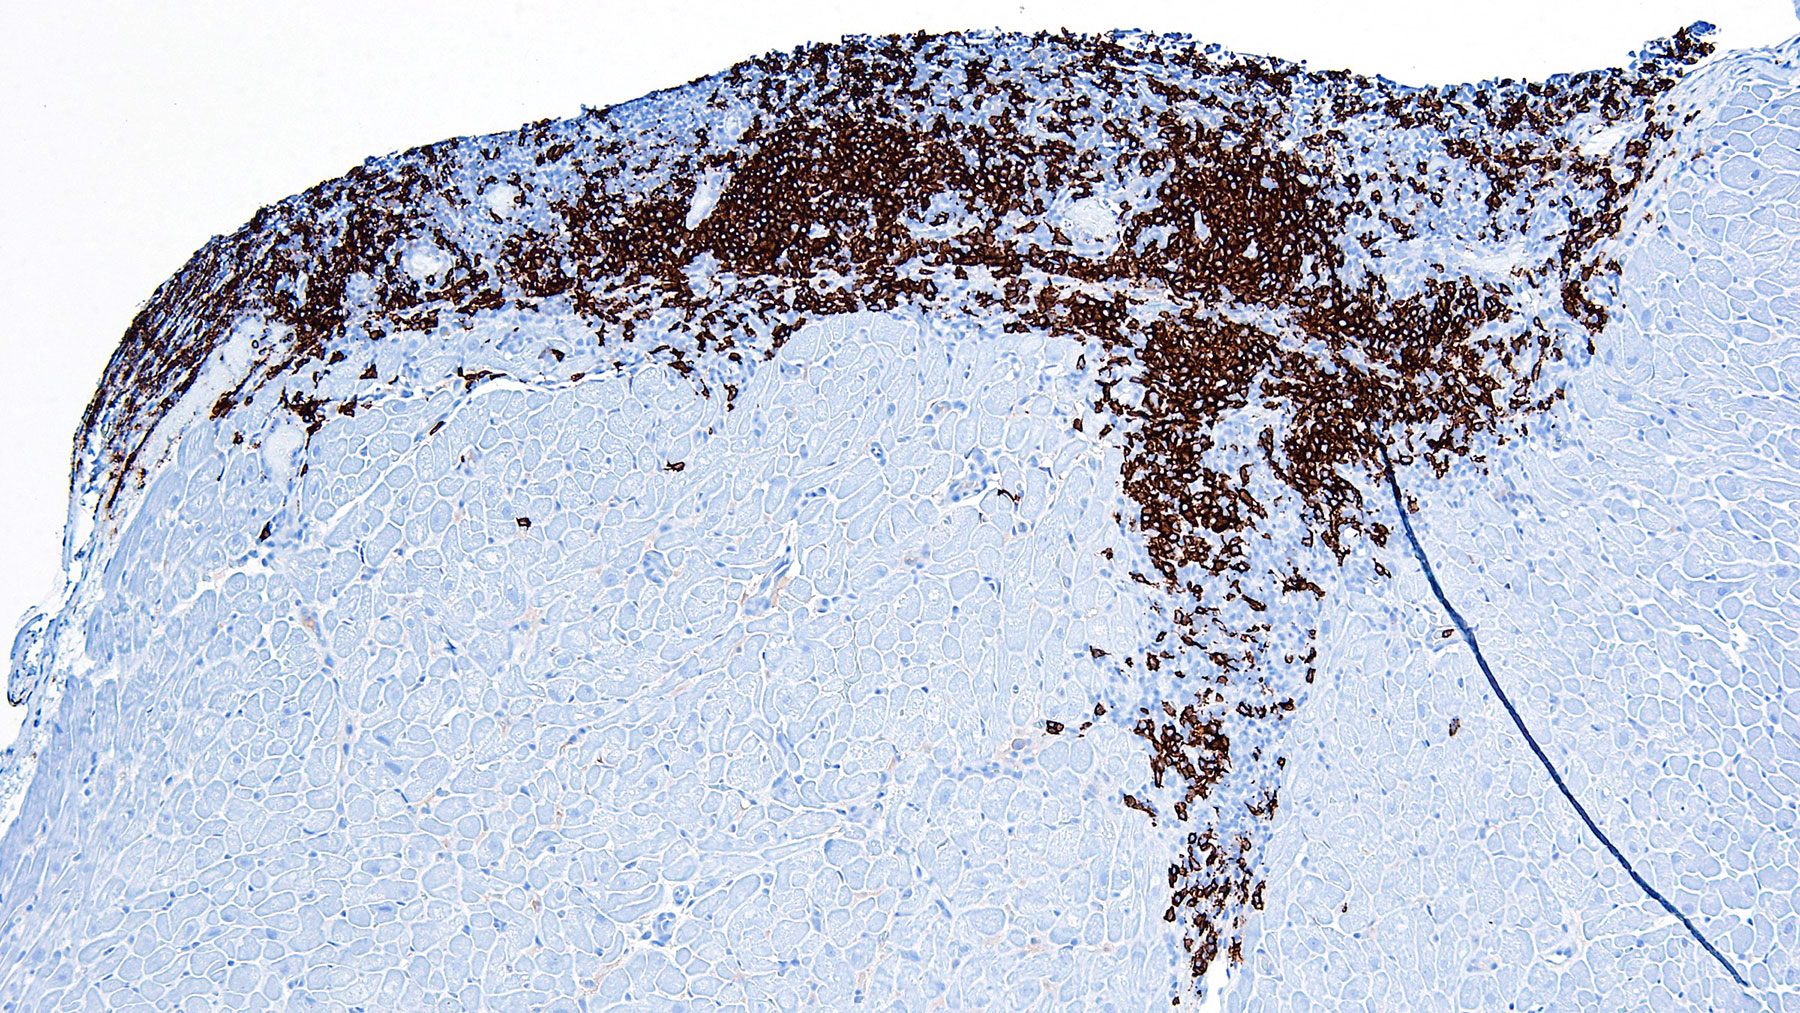

Figure B. CD20 (10x)

Histology: Figure A shows endocardium with a large focus of mononuclear inflammatory infiltrate spreading deeper between the myocardial fibers: this infiltrate shows focal myocyte encroachment and includes some plasma cells and a central capillary vessel. CD4, CD8 and CD20 are all positive (Figure E, F and B). CD21 is also positive which is a strong indicator of quilty effect. (Figures C and D). Trichrome staining shows no significant fibrosis (Figure G)